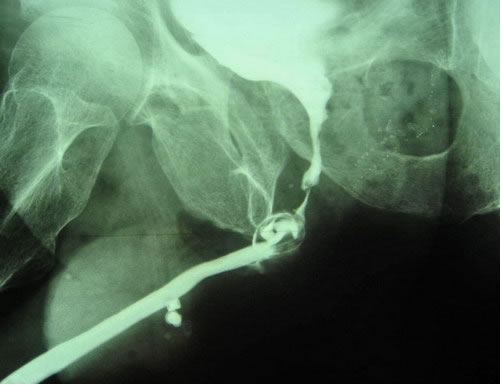

пациентов с данной патологией. В заключении доклада профессор

продемонстрировал несколько клинических случаев и способы

оперативных пособий при повторной установке искусственного

сфинктера мочевого пузыря и удалении сфинктера при развитии

осложнений.